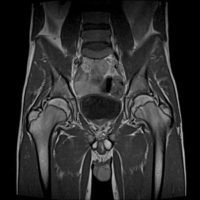

RMN Pelvis

Examinarea iRM pelvina poate depista diferite afectari ale organelor de la acest nivel:

- vezica urinara,

- regiunea recto-sigmoidiana,

- la femei: uterul si ovarele,

- iar la barbati: prostata si veziculele seminale, putand depista prezenta tumorilor, sangerarilor, infectiilor si a diferitelor obstacole.